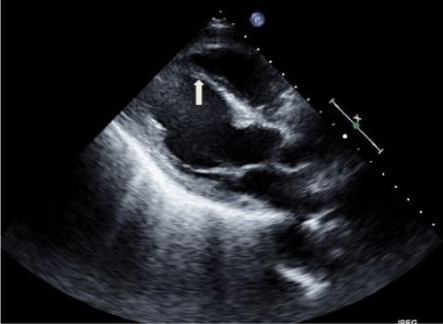

We describe case of a 67-year-old male patient with a history of tobacco and cocaine abuse who presented to the Emergency Department with shortness of breath occurring both at rest and with exertion. Vital signs showed HR of 110bpm, BP 118/70mmHg, respiratory rate of 20/min, O2 saturation of 96% on 2L of oxygen. Physical examination was remarkable for S3 gallop with mild rales over b/l lung. EKG showed sinus tachycardia with significant ST Elevation in leads V2-V5 with significant Q waves in V2-V4. Serial cardiac biomarkers were minimally elevated at 0.9ng/ml. Coronary angiography showed normal epicardial coronary arteries; however, during selective angiography of all 3 major coronary arteries, there was extensive draining of the contrast agent into the Left Ventricular (LV) cavity through many small, diffuse fistulae, resulting in complete LV contrast opacification (Figure 1). Hence, we diagnosed coronary cameral fistula involving all the 3 coronary arteries with each of them draining into LV. The shunt didn’t appear to be large and patient also didn’t complain of any exertional angina, so there was no coronary steal phenomenon and no acute intervention was deemed necessary at this time. Transthoracic echocardiogram revealed decreased LV ejection fraction of 35-40% with a thin akinetic septal and anteroseptal wall (Figure 2). His presentation was consistent with acute systolic heart failure due to prior MI and ischemic cardiomyopathy. He was discharged after improvement with a follow up in 1 week for electrophysiologic studies and possible intra cardiac defibrillator placement.

Figure 2: Transthoracic echocardiogram in parasternal long axis view showing thin septal and antero-septal wall (arrow pointing to inter ventricular septum) suggestive of old myocardial infarction. LA = left atrium, LV = left ventricle, RV = right ventricle